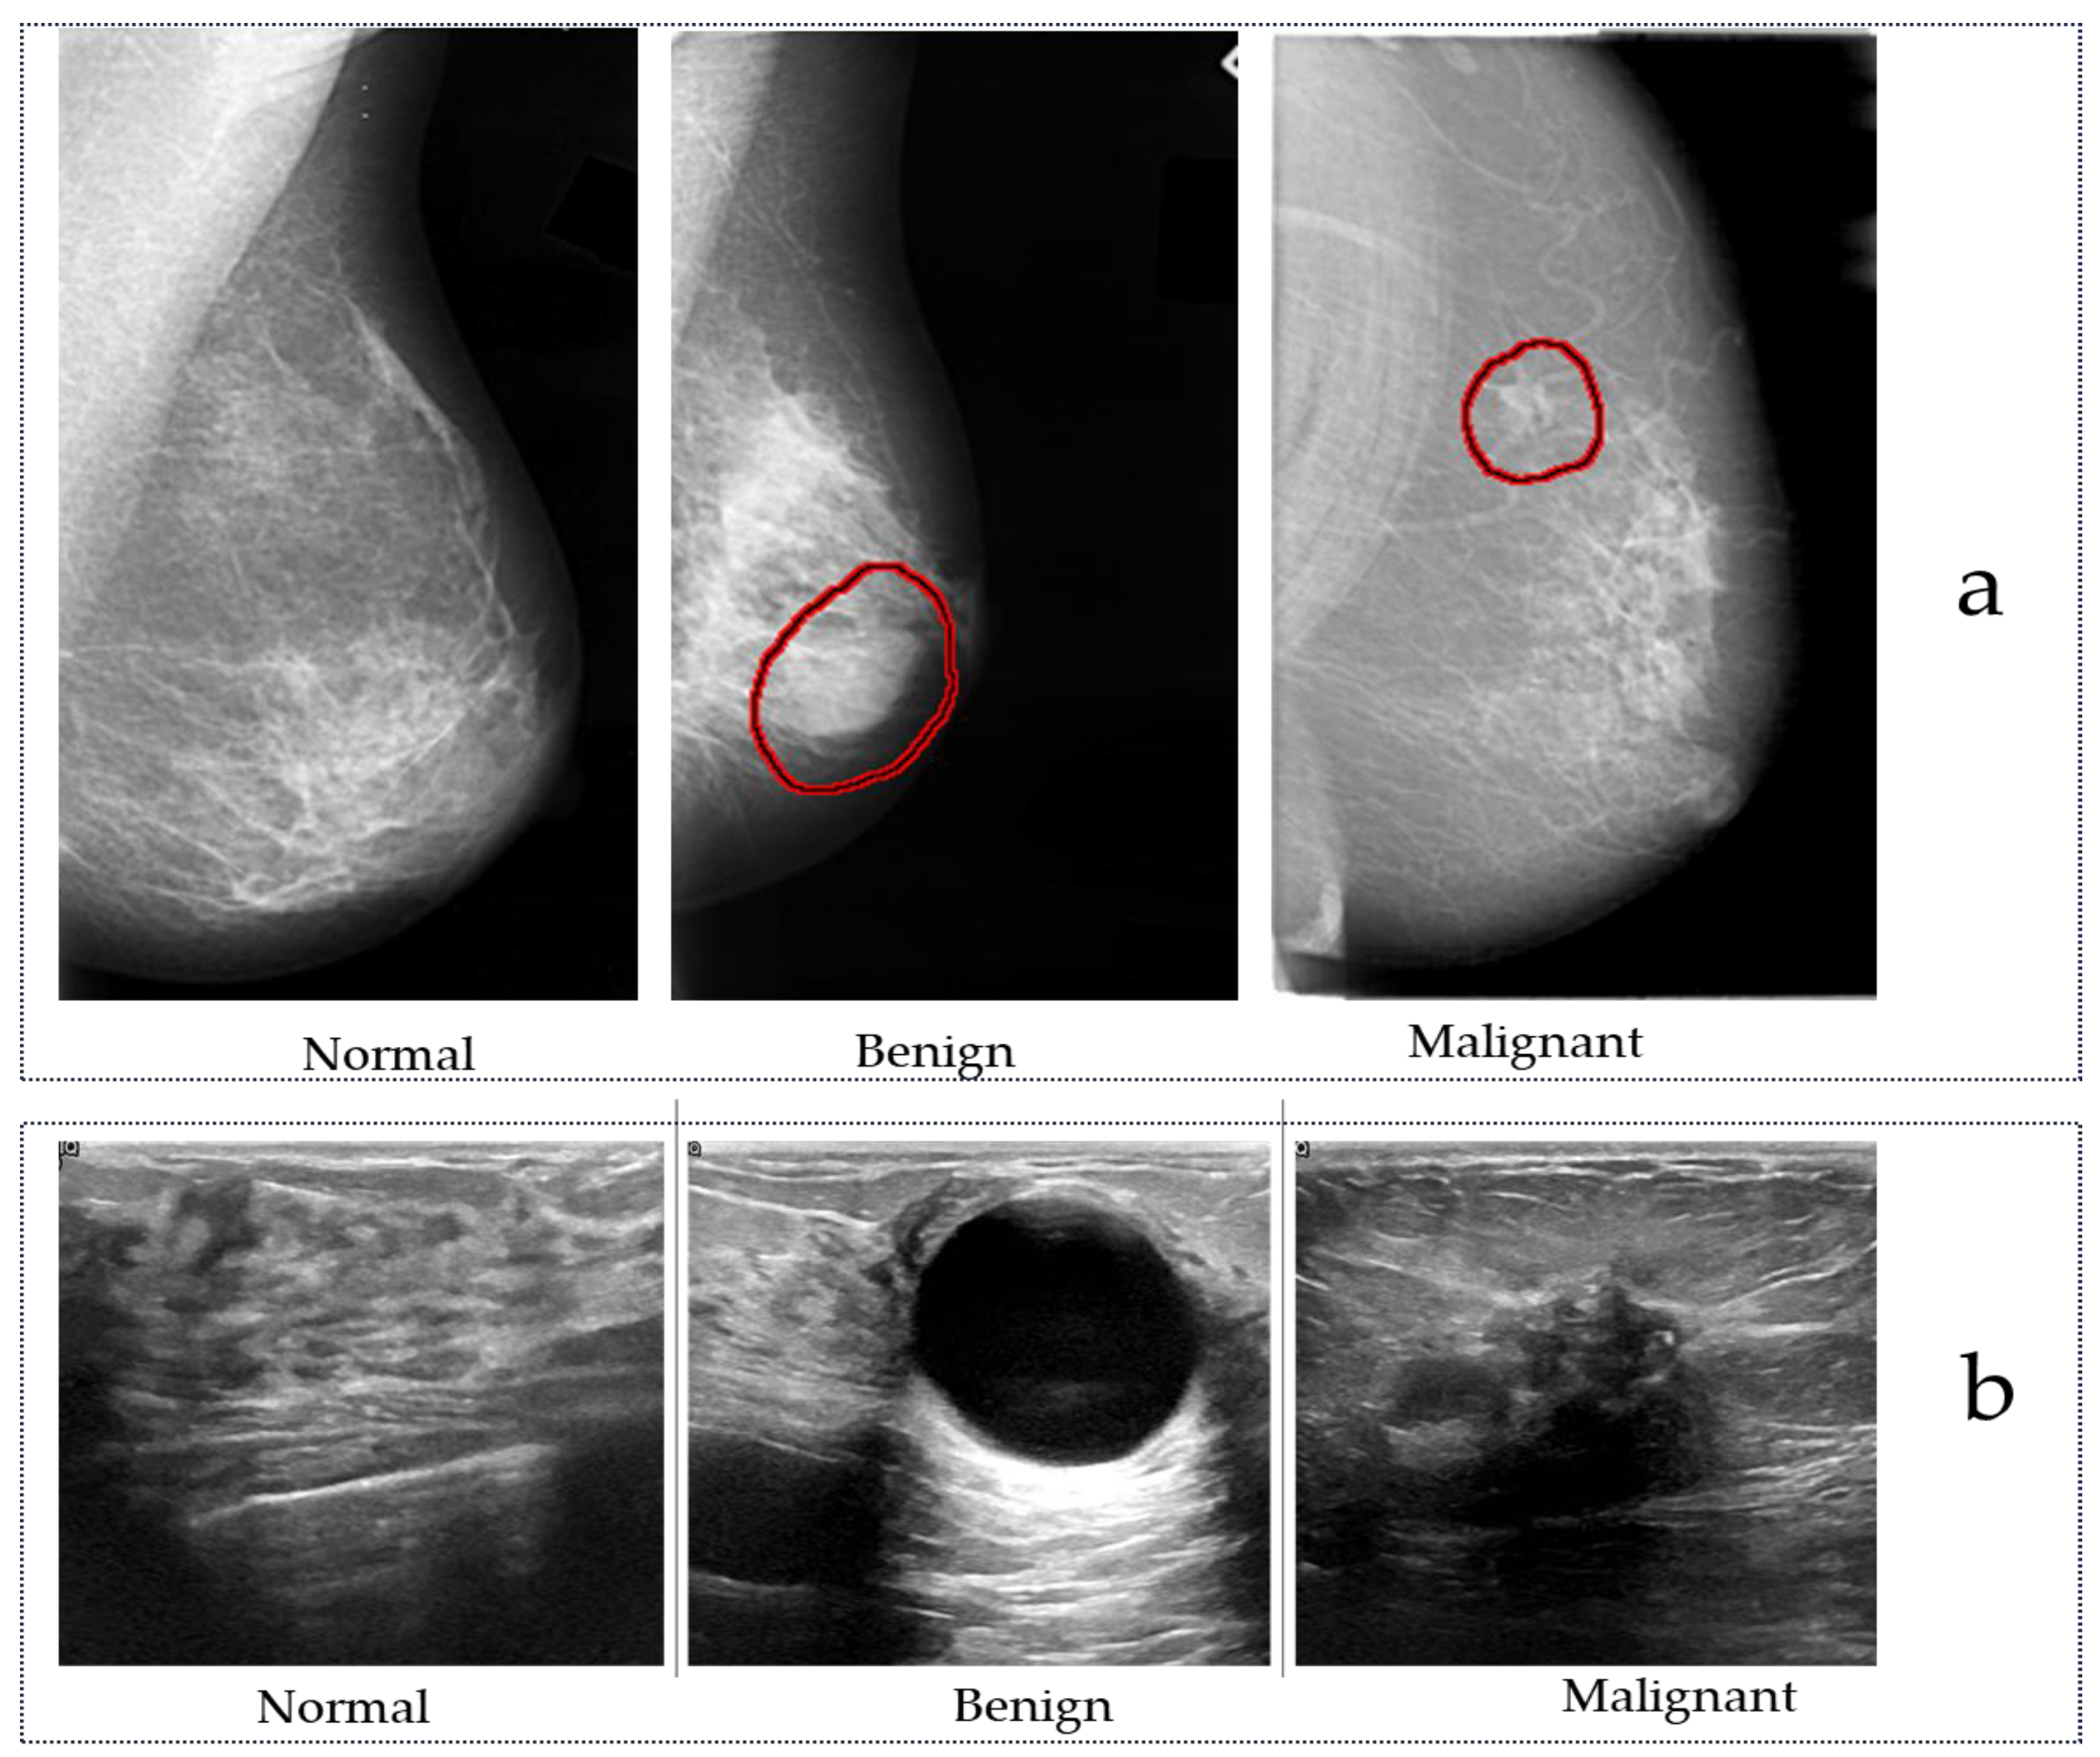

2. Public Breast Cancer Datasets

2.1. Public Mammography Datasets

2.2. Public Ultrasound Datasets